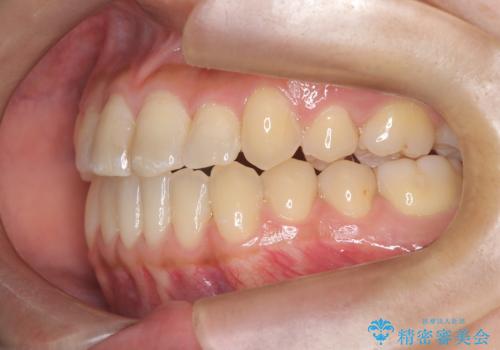

治療開始時はインビザラインを使用し、全体の歯並びを整えながら抜歯スペースを活用して歯を後方へ移動させました。しかし、左上の八重歯のねじれが強く、マウスピースのみでは十分にコントロールできないことが判明。そこで、より細かく歯を動かすために上顎のみワイヤー矯正へ切り替えました。ワイヤー矯正によって翼状捻転も改善し、最終的にバランスの取れた歯並びと噛み合わせを実現。患者様からは「長い治療だったけれど、しっかり整って満足」と嬉しいお言葉をいただきました。